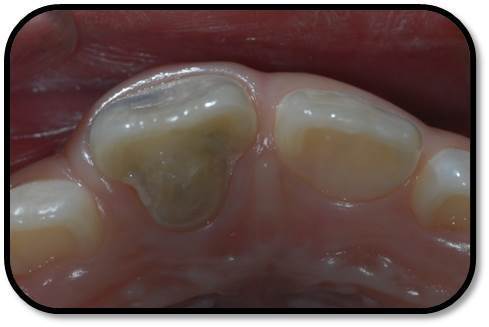

检查: 右上1牙冠略宽大,舌侧见粗大的畸形舌尖,叩痛(++),松Ⅰ°,唇侧牙龈红肿前庭沟膨隆扪痛,挤压唇侧龈缘溢脓,冷热测无反应,右侧上下1侧方颌,正中颌颌创伤。 X线:右上1发育7-8期,根管平行状,根尖孔宽大,约5-6mm宽,根尖周低密度影。髓腔根管宽大内见倒置牙影像,倒置牙可见髓腔。 余牙未见异常 6均已萌出建颌

随访复查: 治疗完成后1个月复查:右上1临床检查无阳性体征,叩痛(—),冷测无反应,无松动,牙龈无红肿,充填物完好,牙冠略有变色, X线检查:牙根根继续发育,可见钙化影像形成,如图示 治疗完成后7个月复查:临床检查无阳性体征,充填物完好,牙冠变色局部发黑,叩痛(—),冷测无反应,无松动,牙龈无红肿,临床及 X线检查:牙根继续发育,如图示 治疗完成后17个月复查:临床检查无阳性体征,充填物完好,牙冠变色局部发黑,叩痛(—),冷测无反应,无松动,牙龈无红肿。X线:牙根继续发育,根尖孔已近闭合。如图。 讨论: